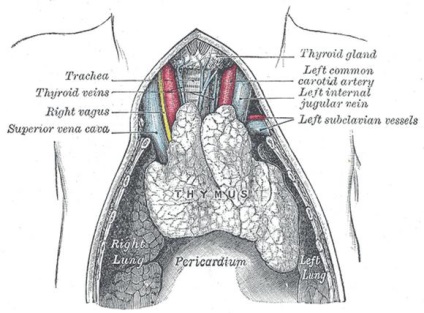

Általában thymomegaly tüneteket figyeltek meg a gyermekek akár 3-6 évig. Ezt követően, azok vagy eltűnnek, vagy átalakítják más betegségek. Thymomegalia gyermek képviseli a proliferációját thymus (csecsemőmirigy).